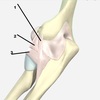

3

4

5

Perfectly

15